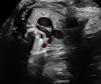

Se presenta el caso de una gestante saharaui, sin antecedentes personales ni familiares de interés. En el embarazo actual el feto presenta crecimiento intrauterino retardado (p<3) con redistribución de flujos. En la ecografía de control a las 38+1 semanas se detecta dilatación aneurismática de ductus arterioso (DAA) (figs. 1 y 2), por lo que se indica finalizar la gestación e ingreso en Neonatología para monitorización, debido a las potenciales complicaciones que puede asociar (incluida rotura espontánea, tromboembolismo, erosión de las vías respiratorias, infección, compresión de estructuras adyacentes e incluso la muerte)1,2.

Ecografía prenatal. Modo 2D. Plano tres vasos-tráquea. La «V» que forman Aorta y Pulmonar se sitúa en zona superior e izquierda de la imagen. Se visualiza ductus arterioso con dilatación sacular de aspecto aneurismático, con diámetro transverso de 10mm.

Estructuras: 1. Arteria pulmonar; 2. Arteria aorta; 3. Cava Superior; 4. Ductus; 5. Tráquea.